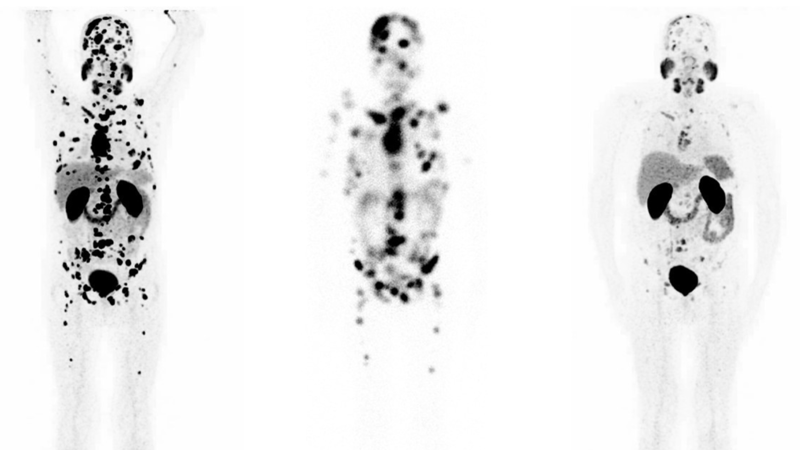

„Ein solcher ‚Strahler‘ ist zum Beispiel Lutetium-177“, erklärt Samer Ezziddin. Der Professor für Nuklearmedizin an der Universität des Saarlandes und Direktor der Klinik für Nuklearmedizin am Universitätsklinikum des Saarlandes ist Spezialist für die sogenannte Radioligandentherapie, bei der radioaktive Substanzen wie zum Beispiel Lutetium in die Tumoren eingeschleust werden und diese von innen millimetergenau bestrahlen. „So wird umliegendes Gewebe verschont und der Tumor und die Metastasen werden sehr punktgenau zerstört“, erklärt er die Wirkungsweise. Mit einer Halbwertszeit von rund einer Woche strahlt das Lutetium-177 also für zwei bis drei Wochen mit nachlassender Intensität. Eingeschleust in die Tumoren wird es über das Antigen PSMA, das insbesondere für Prostatatumoren kennzeichnend ist. „Auf diese Weise wird sichergestellt, dass die Substanz nur die schädlichen Tumorzellen bestrahlt und nicht das umliegende gesunde Gewebe“, erläutert Samer Ezziddin.

Die Ergebnisse sind vielversprechend: „Bei über 50 Prozent der Probanden konnten wir einen PSA-Abfall um mehr als die Hälfte feststellen“, fasst Samer Ezziddin ein zentrales Ergebnis zusammen. Der PSA-Wert ist beim Prostatakrebs der Indikator für die Tumormasse, die im Körper vorhanden ist. Reduziert er sich um mehr als die Hälfte, heißt das, dass der Tumor und seine Metastasen in erheblichem Maße geschrumpft sind. „Bei rund einem weiteren Drittel der Patienten war der PSA-Rückgang zwar geringer als 50 Prozent, aber zumindest konnten wir hier durch das Lutetium-177 ein weiteres Wachstum des Tumors unterdrücken“, erläutert der Nuklearmediziner.

Damit haben er und sein Team in einer Studie in seltener Größenordnung die Wirksamkeit einer Lutetium-177-Therapie für Patienten, die konventionell bereits austherapiert waren, untermauern können. Durch die präzise Bestrahlung und die Schonung anderer Körperregionen kommt es auch zu so gut wie keinen Nebenwirkungen. Im Schnitt konnten die Mediziner nach zwei Gaben Lutetium die größten Effekte nachweisen.